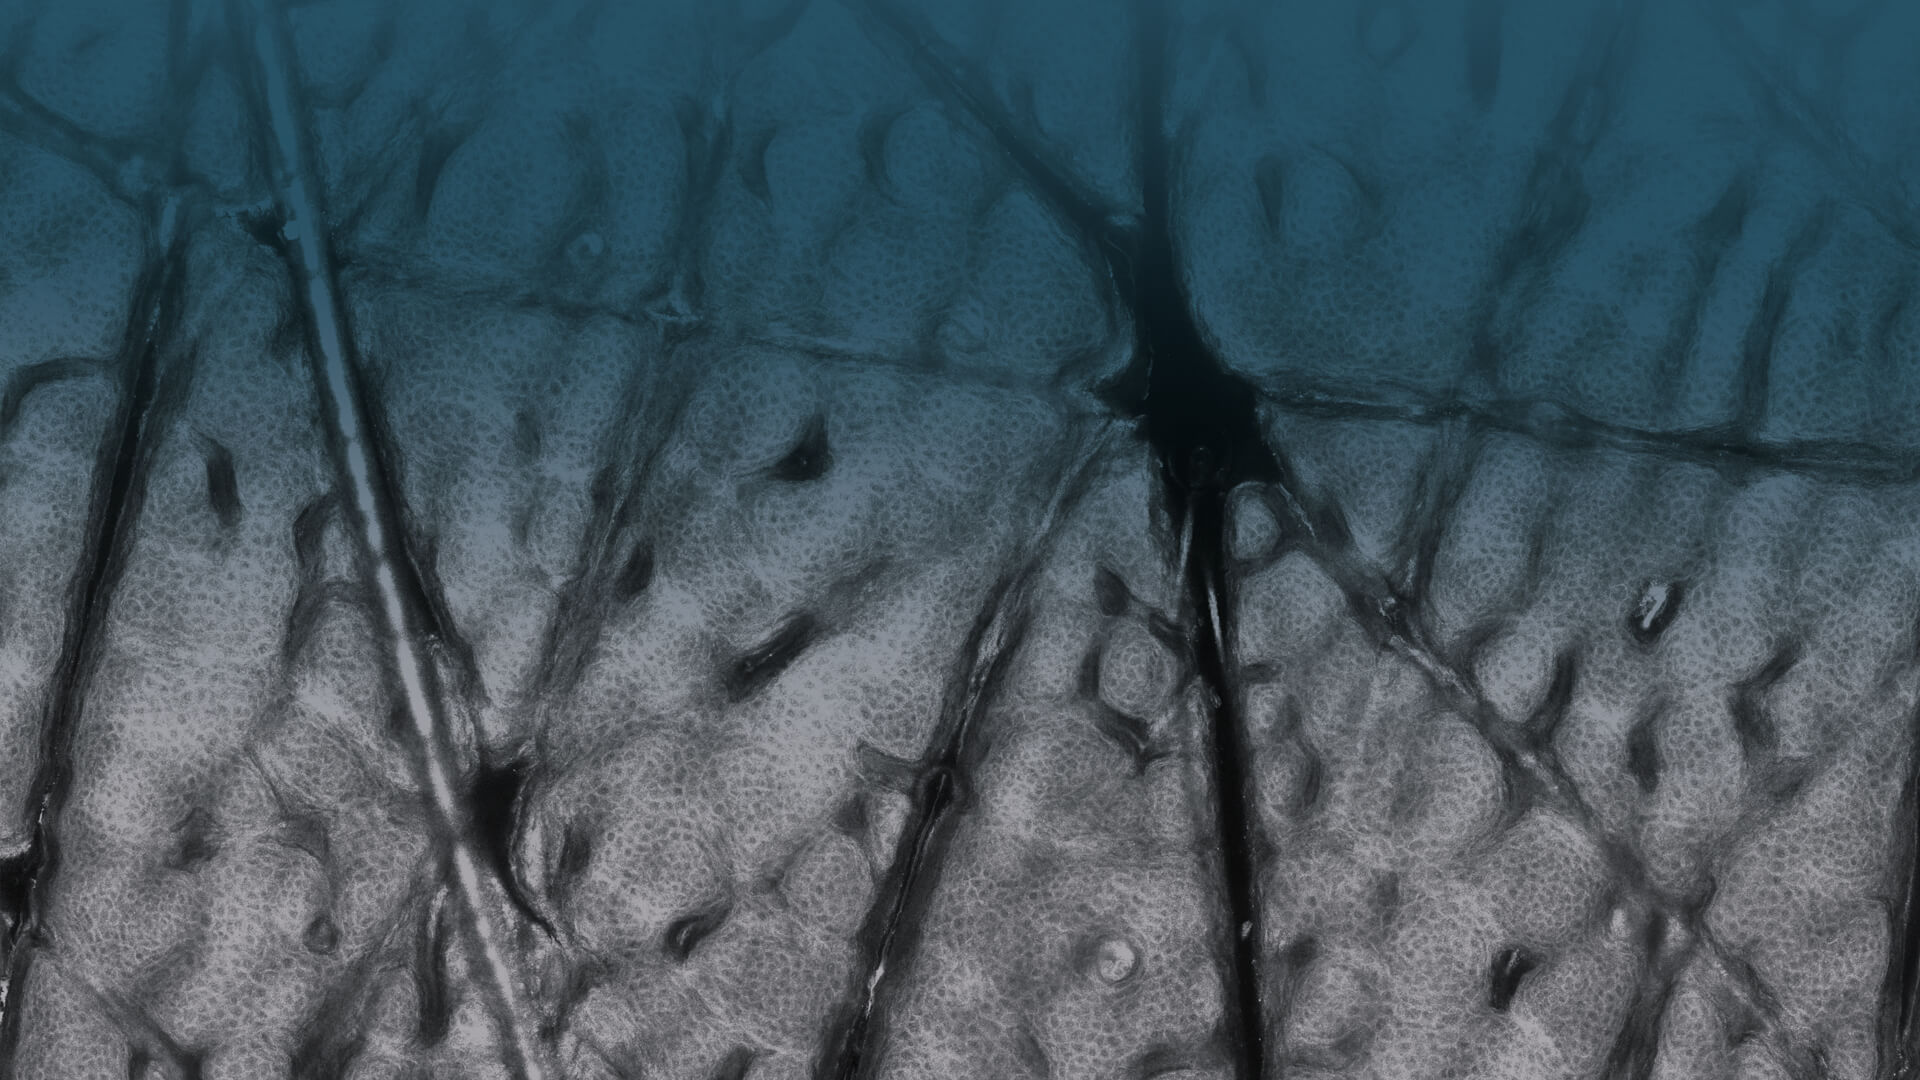

In Vivo examinations using confocal laser scanning microscopy (CLSM) allow for an optical biopsy using a non-invasive procedure. Cellular microstructures of skin can thereby be depicted cell by cell in clearly defined horizontal “optical cross-sections” with a thickness of less than 5.0 μm.

Examining with the VivaScope means both, sparing patients from painful and potentially unnecessary removal of tissue and long waiting time for the result of an examination. The examination opens a “window into the skin” without causing pain or damaging it.